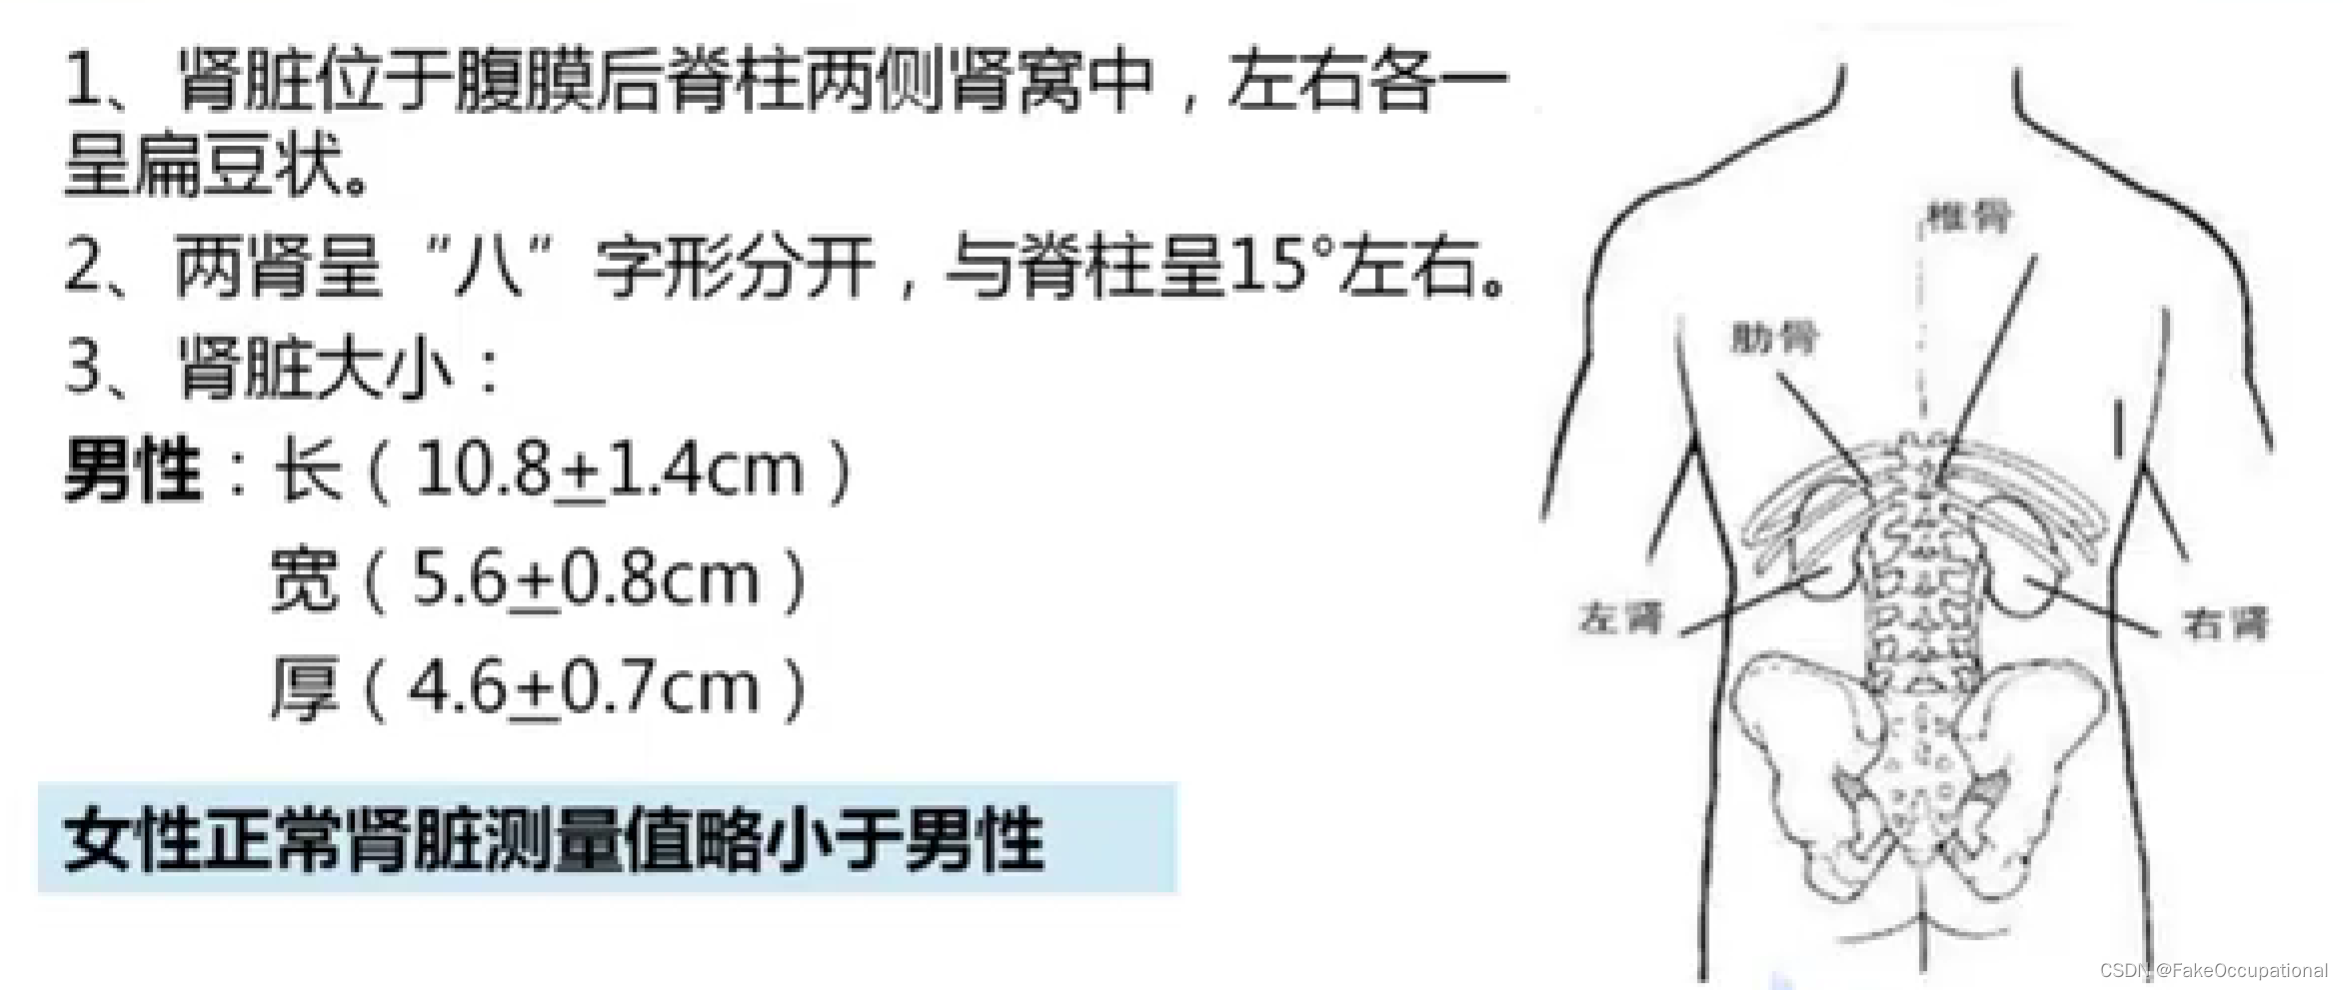

肾脏解剖概要